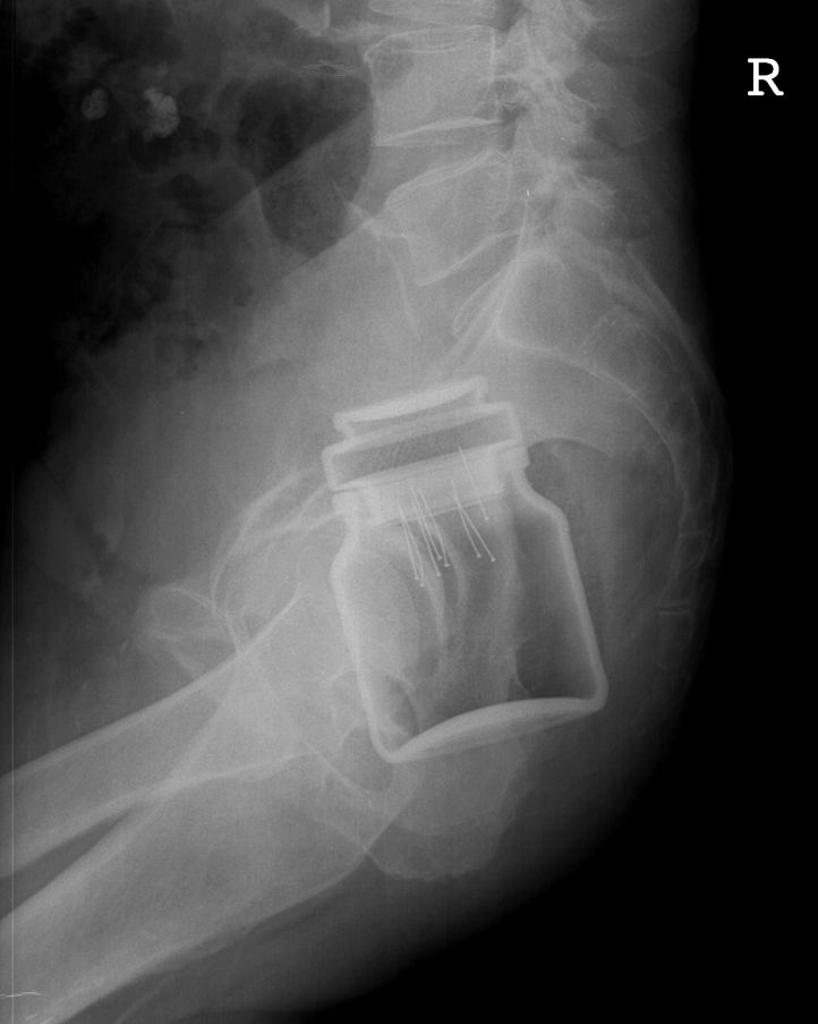

Strange object 01.jpg Strange object 02.jpg Strange object 03.jpg Strange object 07.jpg Strange object 10.jpg Подборка странных предметов, обнаруженных в человеческом теле. Пожалуй, элемент смешного присутствует ))) Хотя "носителям" вряд ли до смеха. )) Впрочем, кто им виноват?